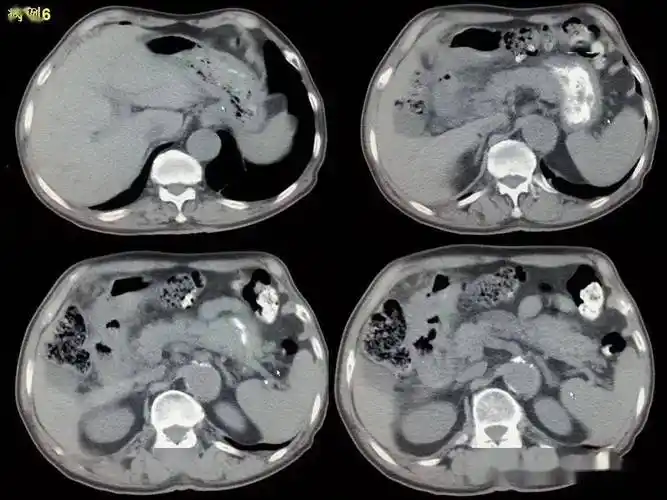

消化道穿孔ct影像大汇总看完印象深刻